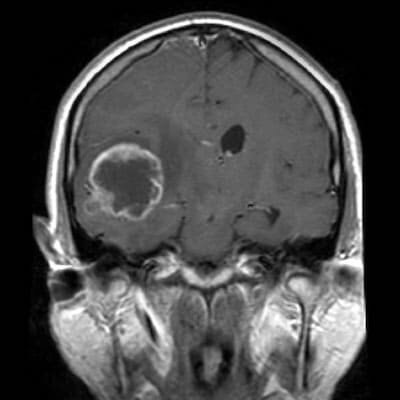

Глиобластома на МРТ

При подозрении на глиому очень важно сделать МРТ головы именно с контрастом. По тому как клетки мозга будут накапливать контрастное вещество, рентгенолог может сразу сказать, где локализация новообразования, есть ли метастазы, является ли опухоль злокачественной или доброкачественной, есть ли признаки диффузной глиомы или некроза. Магнитно-резонансное исследование, будучи неионизирующим видом диагностики в отличие от рентгена и КТ, не может никаким образом спровоцировать рост раковых клеток. Магнитное поле томографа не оказывает никакого излучения или вредного воздействия на организм человека. Поэтому МРТ головного мозга признано безвредным методом обследования, и данной диагностике отдается предпочтение при исследовании детей, беременных, а также при необходимости многократных повторных обследований.